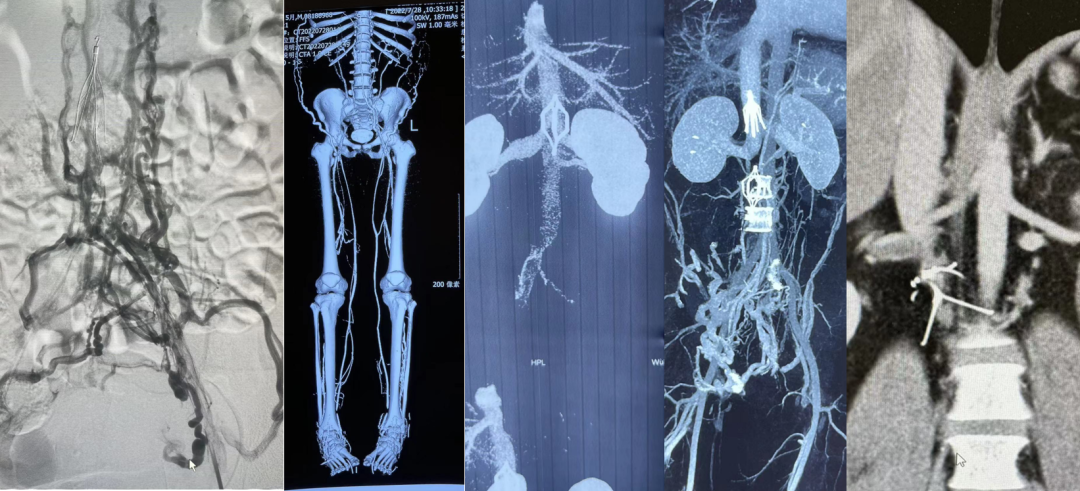

图:不同滤器、不同时期的血栓处理策略

★ Case1:梭形滤器下腔静脉亚急性血栓

图:基线造影情况:右侧股静脉、双髂静脉、下腔静脉血栓性闭塞

图:AngioJet +手动抽吸血栓

图:抽吸后双髂静脉及下腔静脉复通+滤器置换

图:足量抗凝两周后回收临时滤器

图:2年后随访结果